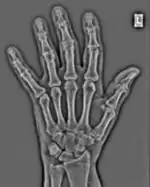

The essence of this approach is that it can be used to produce a range of image processing effects by enhancing and/or suppressing features in the 2D-FFT and then converting the result back into the spatial domain using the IFT, as illustrated in Figure 1.28. Such image manipulations are considered in more detail in a later chapter. Note that the form of image processing demonstrated in the figure is for purely illustrative purposes and bears no direct medical significance.

Fig. 1.28(a): A radiograph of the wrist.

Fig. 1.28(b): The wrist radiograph processed by attenuating periodic structures of size between 1 and 10 pixels.